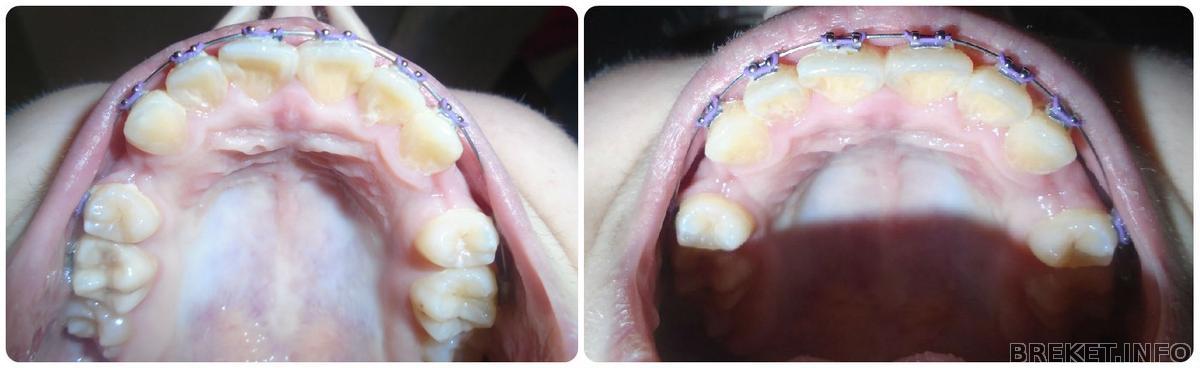

1.5 месяца

Вот уже и 1.5 месяца прошло.... Зубки двигаются медленно, но в верном направлении... Чему я конечно рада... Не по теме, но у меня очень сильно сохнут губы, ничего не помагает, может подскажите, чем вы пользовались)Ну а пока фотки для сравнения.... На первом коллаже разница 3 недели, на втором 2. А на последнем фото в один день только немного с разных ракурсов.

Изменения есть или мне кажется?

Ни чуть не кажется! =) Единички уже чудесно развернулись!